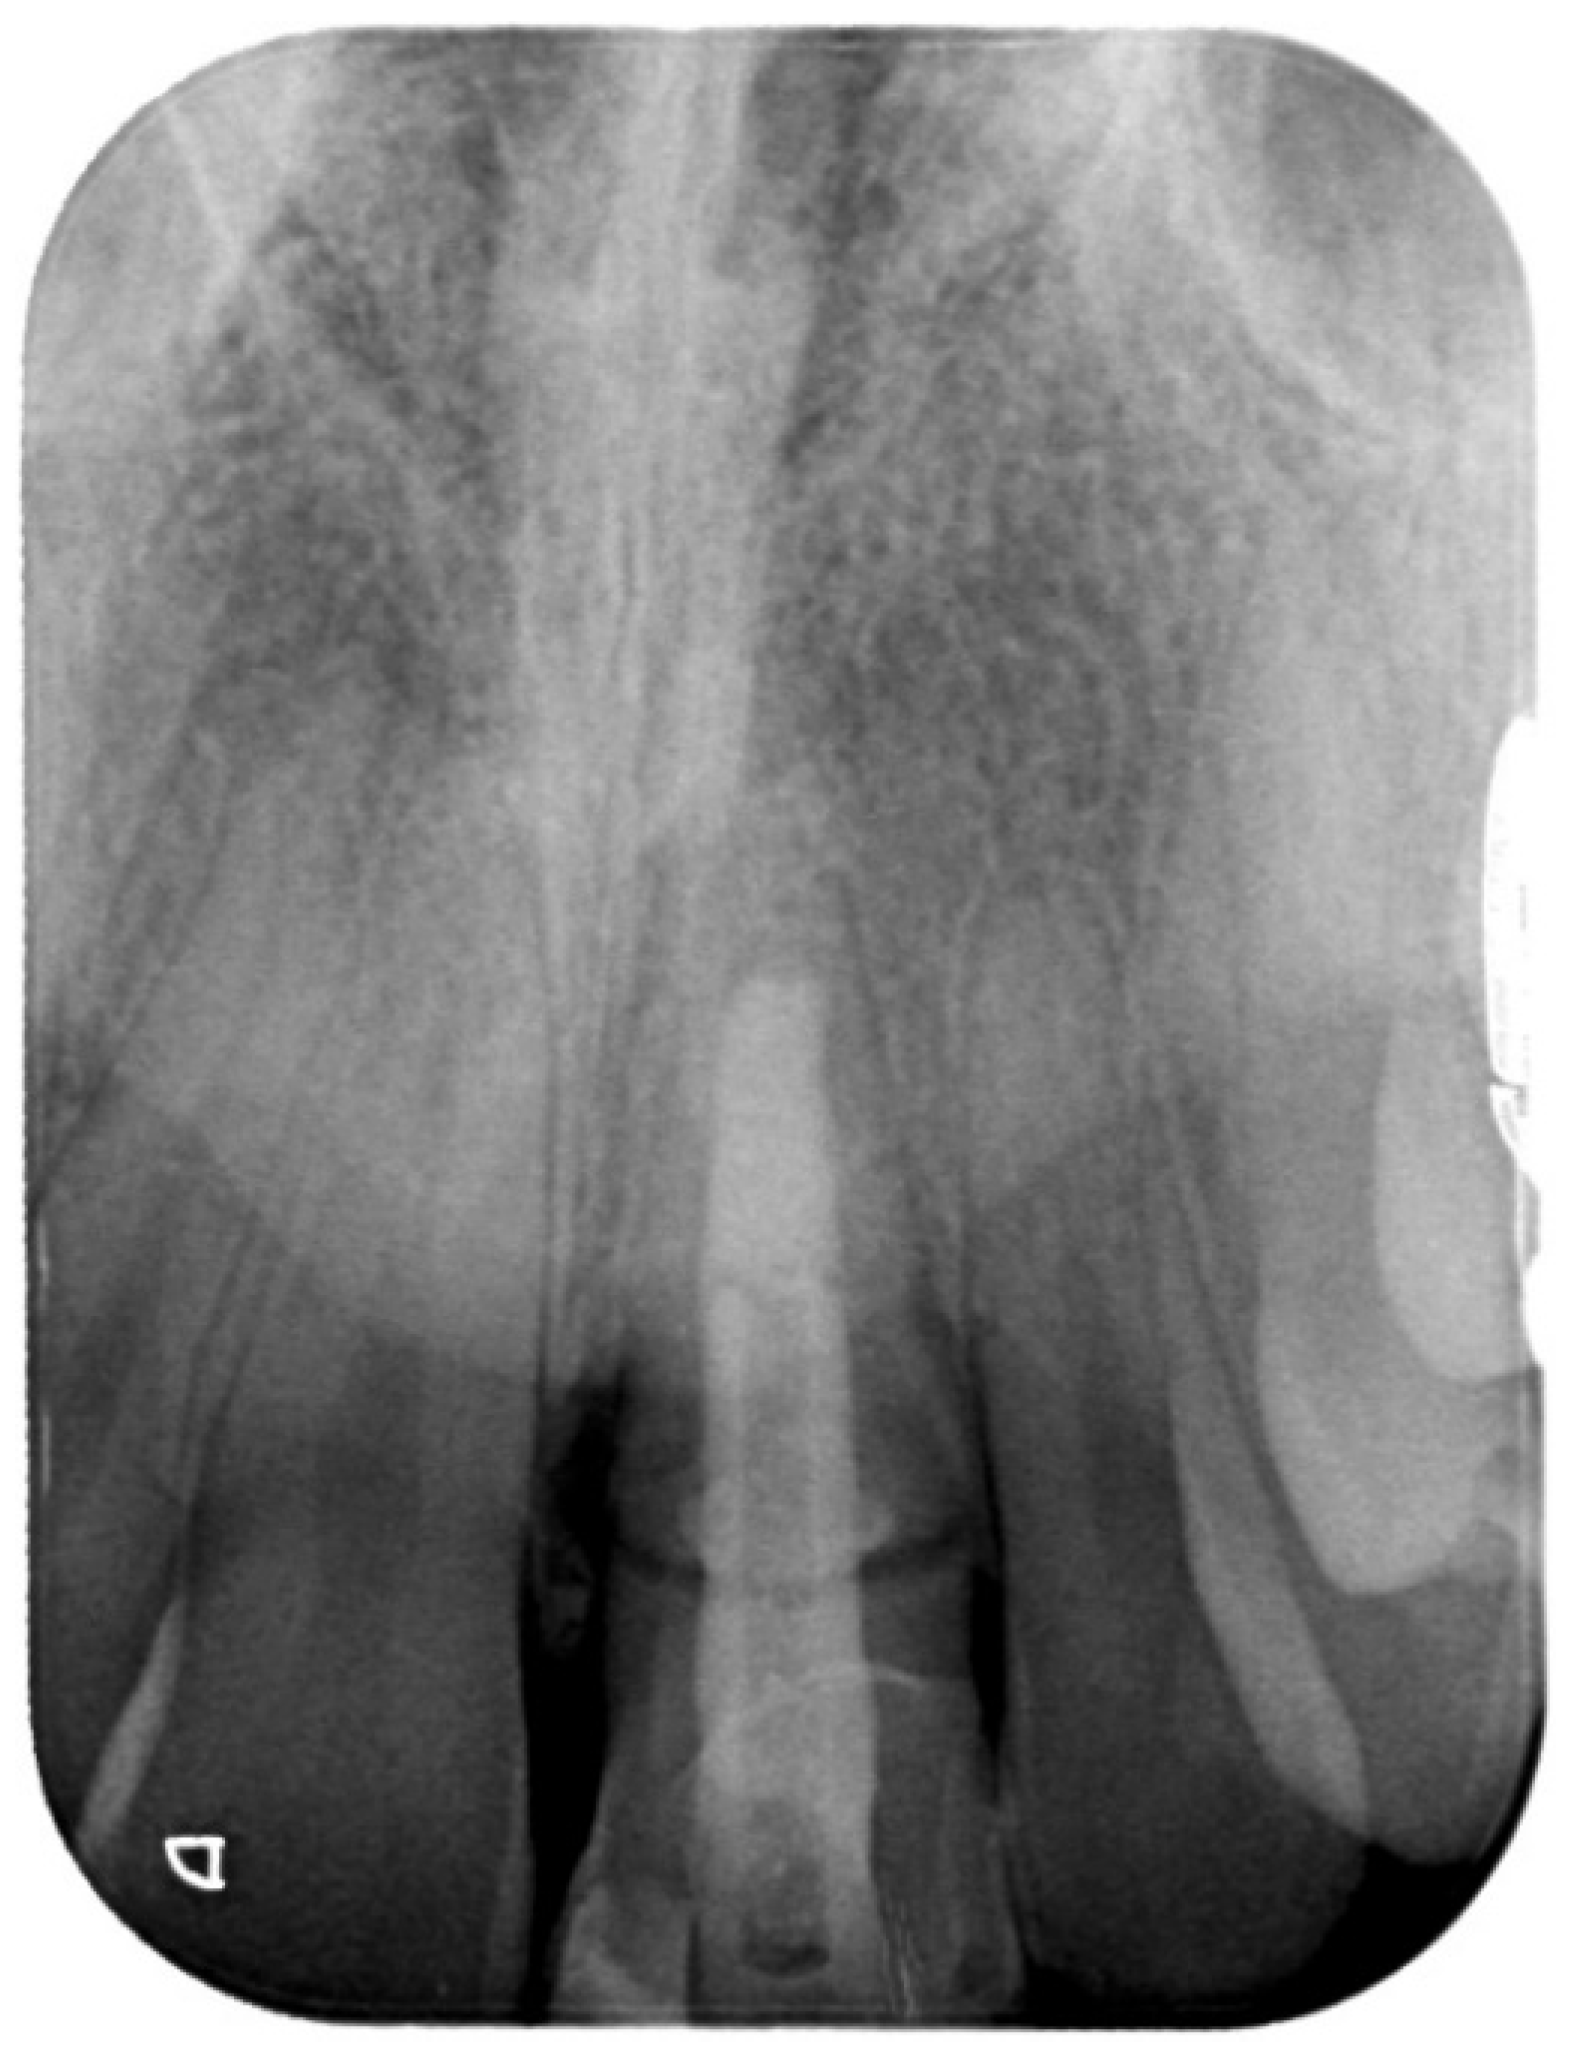

2. Case Presentation